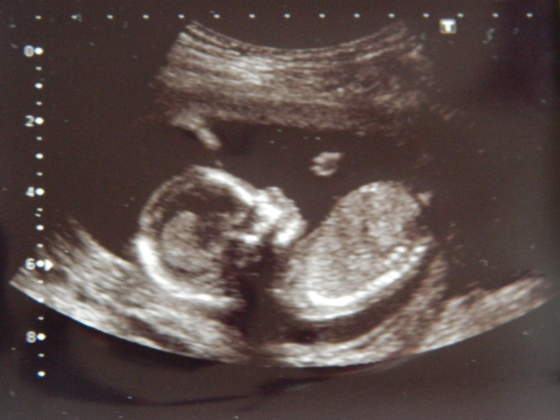

Kruszki, piękne zdjęciaA znacie płeć? Bo mi na dziewczynkę wygląda - tak po twarzy

hehehe no to zescie teraz napisalykruszki piękne małe słoneczko, a mnie na chłopczyka wyglądahihi